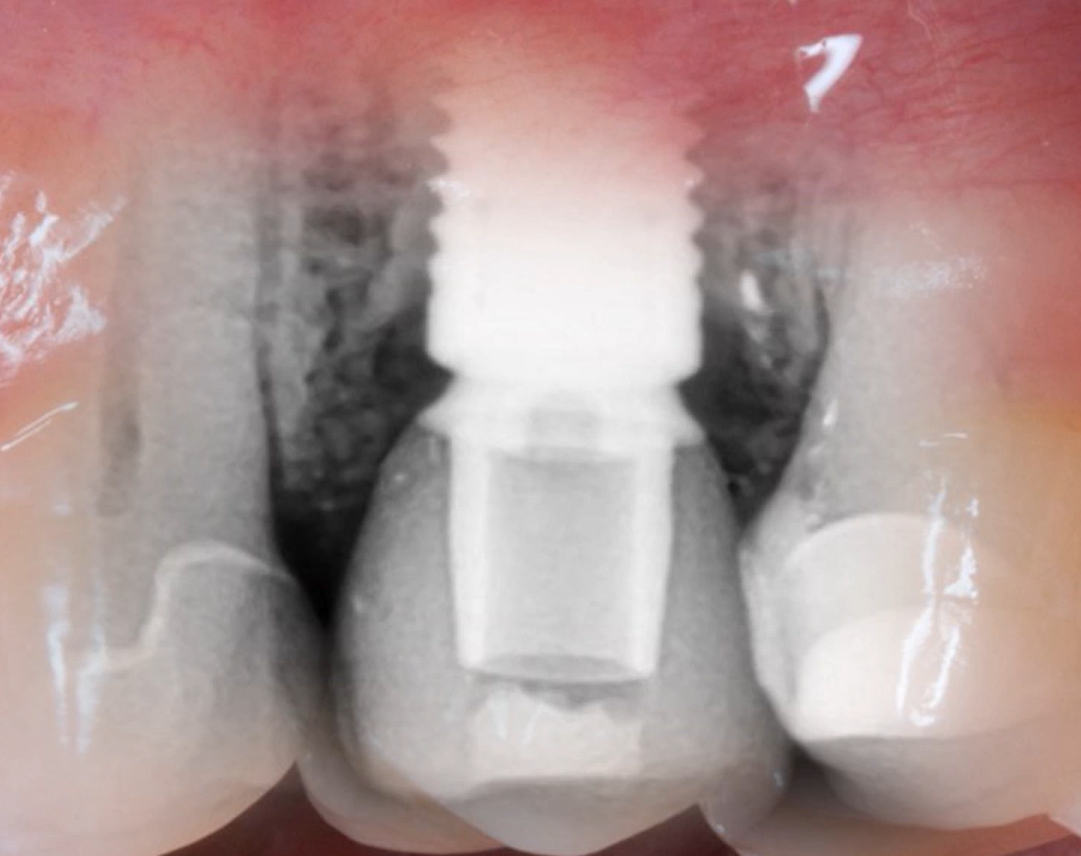

- The relationship between bone loss and the position of the implant/abutment interface. Another interesting study is worth mentioning: Peri-implant Inflammation Defined by the Implant-Abutment Interface. We found that the lower the platform and the implant/abutment connection, the greater the bone loss, and this is confirmed by the results of this study (see the illustration below).

Bone loss with different implant placement methods, but other conditions being the same: minimal loss is observed with supracrestal placement, which is logical and confirmed by other studies; maximum bone loss is observed with subcrestal placement. YouTube/ Implantarium/ Rauf Aliyev

This is due to the fact that the connective tissue connection always forms below the implant/abutment line, so bone remodeling occurs to a greater extent than with other schemes. But as we mentioned earlier, subcrestal placement maintains implant stability when the soft tissue thickness above the alveolar ridge is less than 2 mm. In this case, tissue remodeling still occurs to create a 3-3.5 mm gingival cuff, but the implant neck is not exposed.